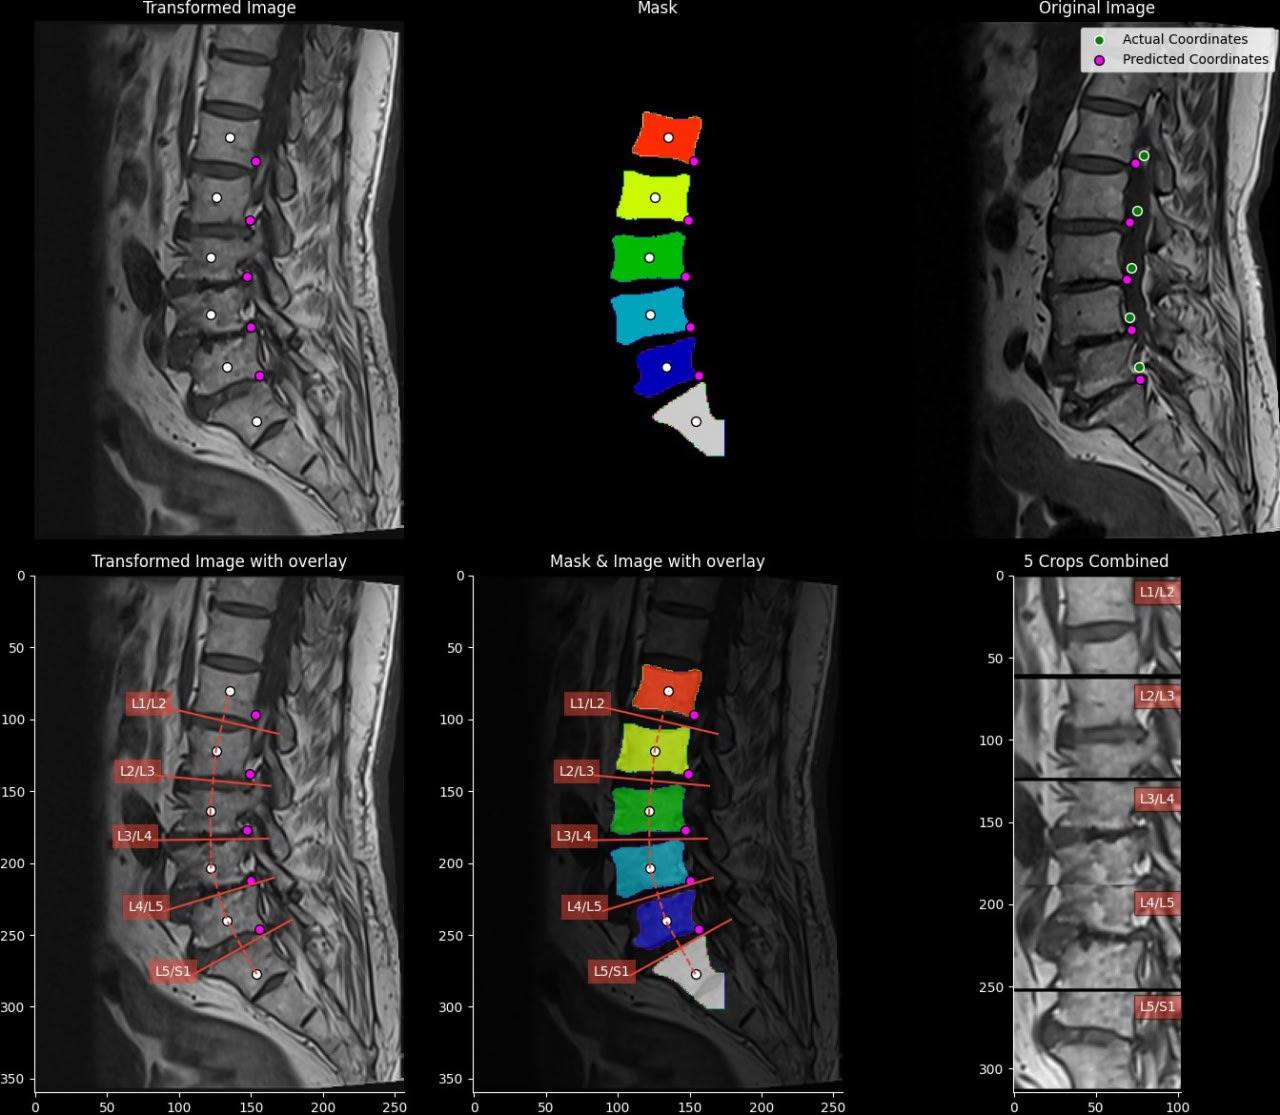

🩻 Первое соревнование проходило в 2024 году и было посвящено Computer Vision в работе с МРТ-снимками спины. В соревновании использовались МРТ-данные позвоночника. Для каждого пациента это был набор последовательных двумерных снимков, которые вместе образуют трёхмерное изображение спины. По этим данным нужно было определить, есть ли защемление поясничных нервов.

▪️сегментация нужных позвонков на вертикальных срезах

▪️сопоставление нужных горизонтальных срезов с детекций

▪️классификация нужных зон на отобранных срезах